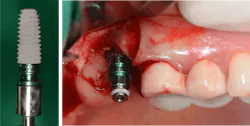

If the bony height defect is not significantly large (residual bone height over 4 mm), a crestal approach is usually adopted. This involves accessing the sinus cavity directly through the dental implant site, typically during implant placement. The traditional osteotome technique, originally proposed in 1994 by Summers,1 involves manually tapping with a mallet specialized instruments into the bone to upfracture the sinus bone and forcibly create space (figures 1 and 2).

While the traditional technique of using osteotomes by Summers is routinely utilized and quite predictable, it poses dangers of inherent complications: